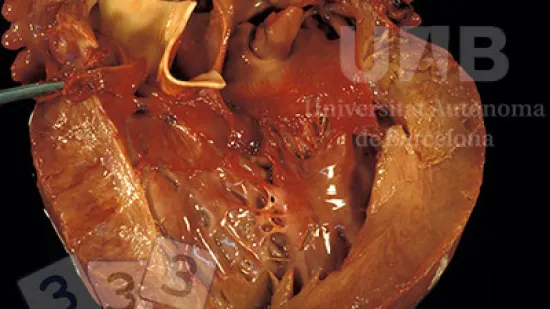

Semaine du 24-Jan-2022

La lésion observée sur ce cœur correspond à...